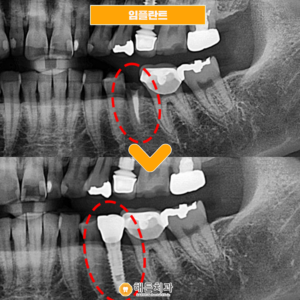

배방역치과 자연치아를 살리기 위해서는 (치료기간 : 2022.03~2022.06) 안녕하세요. 오늘은 저희 배방역치과를 내원하여 임플란트와 치관확장술을 통해 크라운치료하신 환자분을 소개해 드릴까 하는데요. 아래 사진을 보면서 설명해 드리도록 하겠습니다. 배방역치과 위 사진은 고*님의 치아 사진입니다. 고*님은 식사 때마다 통증을 느끼고 불편감을 느낀다고 하여 상담을 원한다고 하셔서 저희 치과에 내원해 주셨는데요, 더보기…